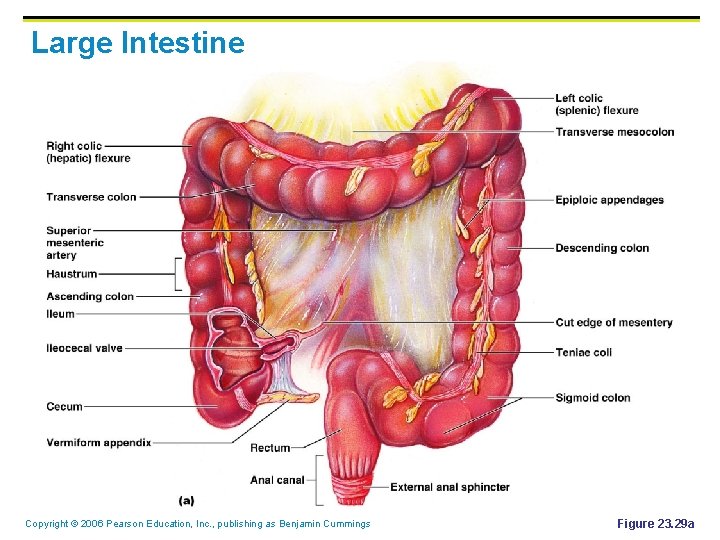

Large Intestine § § Is subdivided into the cecum, appendix, colon, rectum, and anal canal The saclike cecum: § Lies below the ileocecal valve § Contains a wormlike vermiform appendix Copyright © 2006 Pearson Education, Inc. , publishing as Benjamin Cummings

Large Intestine Copyright © 2006 Pearson Education, Inc. , publishing as Benjamin Cummings Figure 23. 29 a